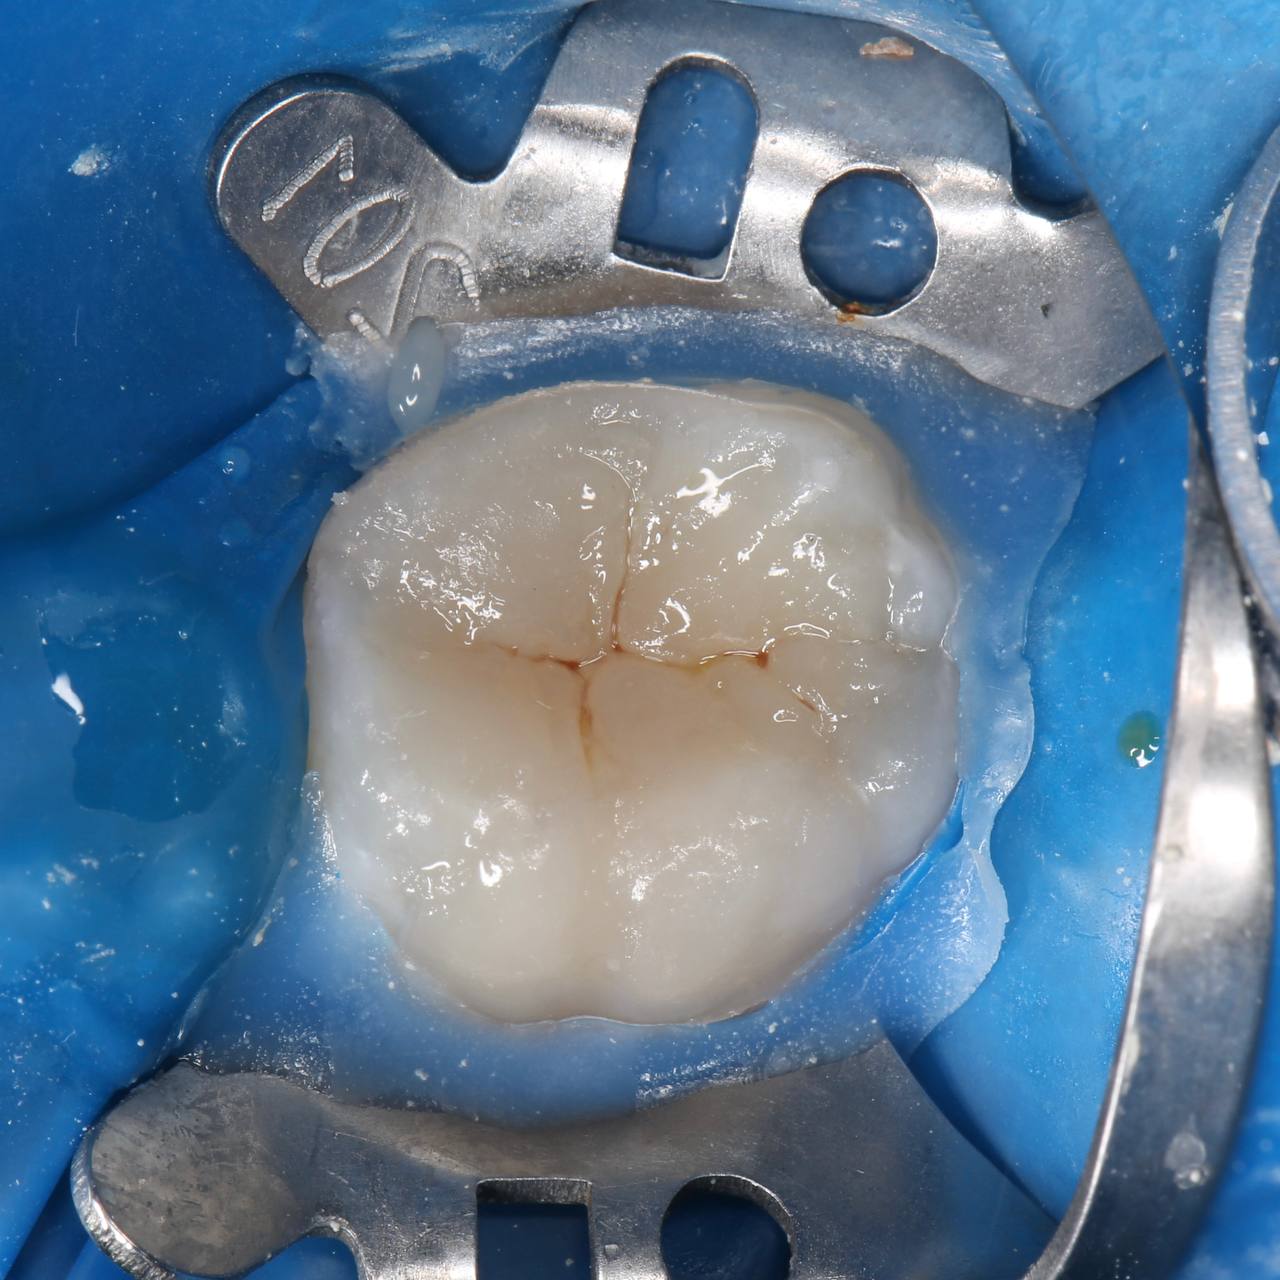

🦷 Облитерация корневых каналов после покрытия рога пульпы неизведанным веществом.